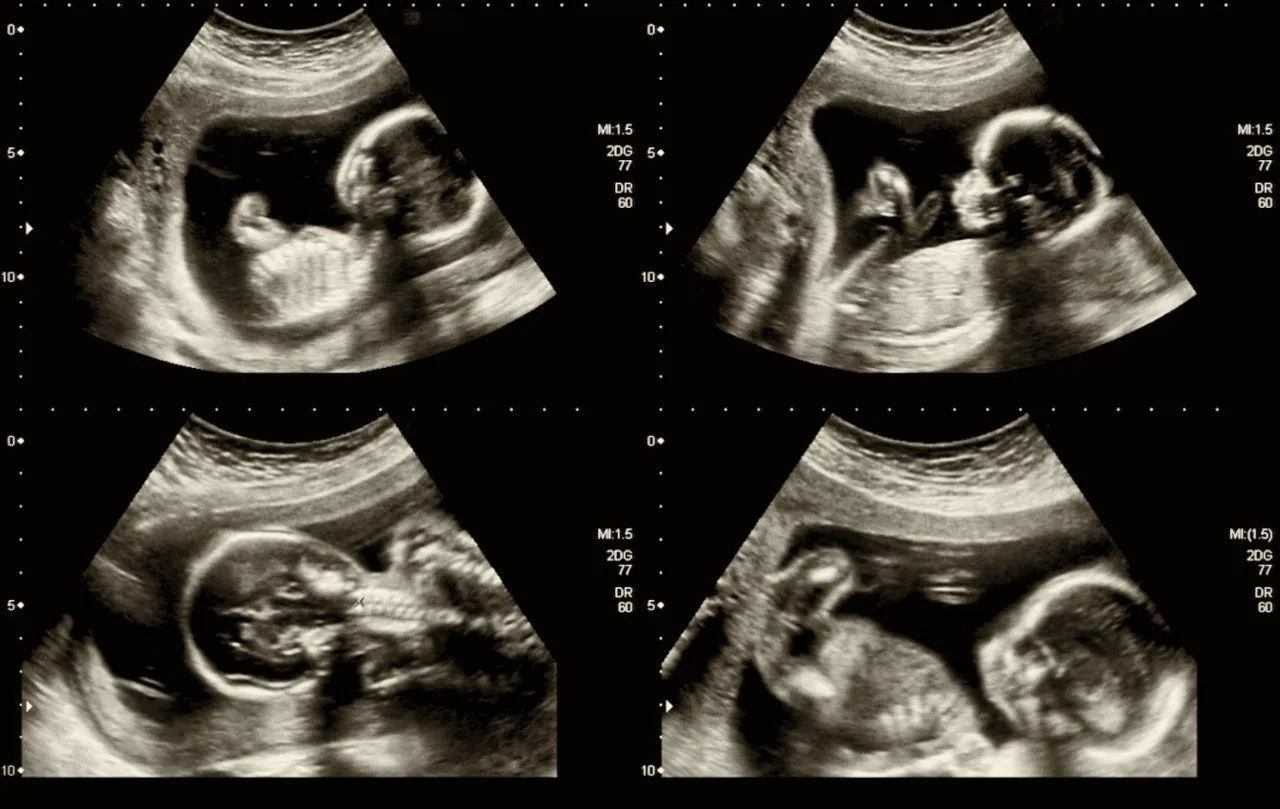

Une grosseur repérée pendant l’échographie

Lors de l’échographie du troisième mois, les médecins ont repéré que le bébé avait une grosseur au niveau de la mâchoire sur le côté droit du visage. Au vu des images, les professionnels ont avancé que la petite fille avait un kyste, une tumeur, un tératome ou encore une dysplasie fibreuse (affection osseuse congénitale caractérisée le remplacement de l'os normal par un tissu fibreux plus fragile).

C’est finalement à la naissance de la petite fille que l’équipe médicale a découvert la véritable nature de la masse visible sur les échographies. Il s’agissait d’une seconde bouche mesurant entre 1 et 2 cm. Cette malformation congénitale est appelée une diprosopie ou duplication craniofaciale. Elle se caractérise par une duplication de certaines parties du visage.